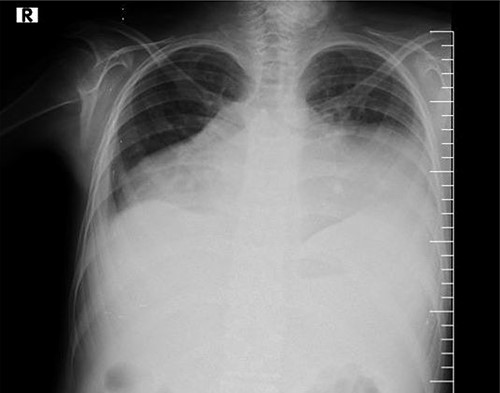

The assessment of the posterior anterior chest X-ray revealed an increased cardiothoracic ratio, a missing heart silhouette and pulmonary edema (Fig. 2). Furthermore, echocardiography evaluation revealed thickened pericardium, massive pericardial effusion, septal bounce and respiratory variation in mitral and tricuspid inflow (Fig. 3A and B).

Chest X-rays show an enlarged cardiothoracic ratio, a lack of cardiac silhouette and pleural effusion.